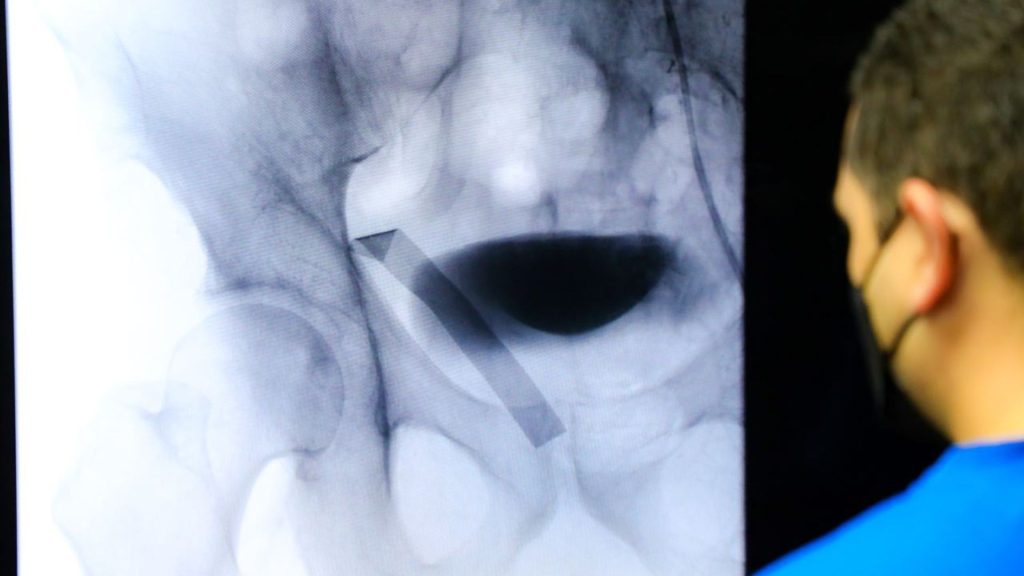

Solo este año serán ejecutados 50 implantes de válvula aórtica en pacientes cardiacos en el ISSS

El Gobierno del Presidente Nayib Bukele le apuesta a procedimientos innovadores en el Instituto Salvadoreño del Seguro Social (ISSS), para 2023, están programadas 50 cirugías para implante de válvula aórtica vía TAVI, con el objetivo de mejorar la calidad de vida de los asegurados que sufren padecimientos cardiacos. Las primeras 13 cirugías serán este mes.